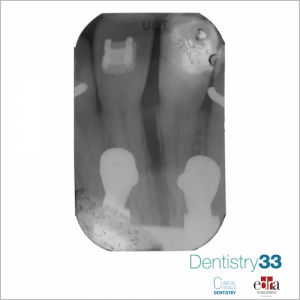

Screw retained crowns to implants are widely used to replace missing teeth. Fracture of the screw is considered one of the most common complication related to this type of prosthesis. Screws can be produced both with cold-rolling and cut threads technique. Since the rolling threads are less common in dentistry compared to industry, Armentia et al. aimed at comparing the mechanical characteristics of both manufacturing techniques. The null hypothesis tested was that rolled threads provide better mechanical response than cut threads.

The authors reported a smoother surface finish, and higher compressive residual stresses for the roll- threaded screws. In addition linear regression models showed a fatigue life 9 times higher for roll-threaded screws (P=1) without affecting static behavior, which showed statistically similar static strengths (P=.54).

According to these results, rolling was demonstrated to be a better thread-manufacturing process for prosthetic screws, producing improved surface quality and fatigue resistance.

(Photocredit: Dr. Federico Del Bianco)